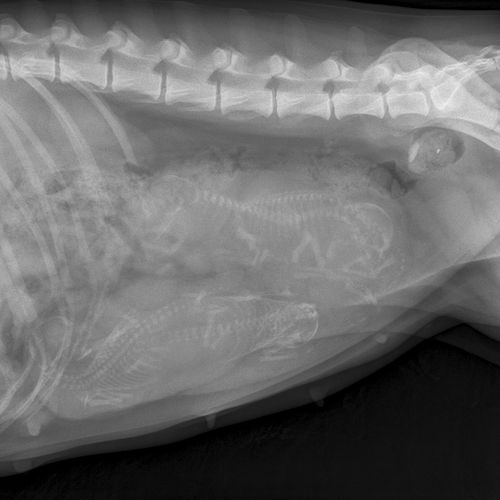

3/21/12 - Did an xray on Rio - she has 4 puppies in there. We new she had about 4 pups from the ultrasound. Wish there were a few more but at least we have puppies!! Puppies due next Tuesday-Thursday, 3/27-29th. Whelping box getting set up this weekend...